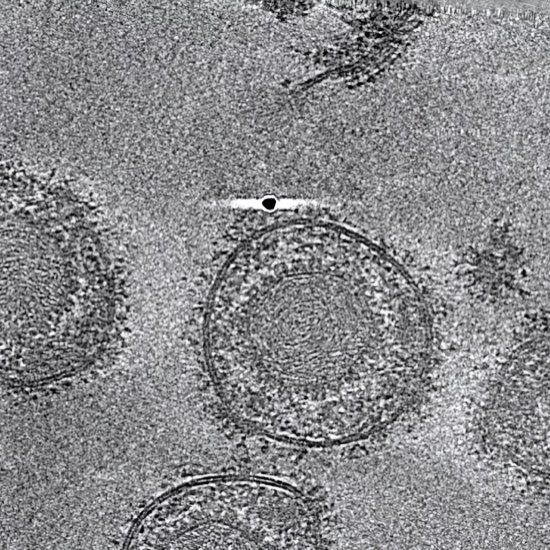

| News • Studie zu Influenza-A-StämmenWarum manche Grippeviren gefährlicher sind als andereManche Influenza-Viren lösen bei einer Infektion schwere Verläufe aus, andere Stämme bleiben dagegen vergleichsweise harmlos. Eine neue Untersuchung zeigt, woran das liegt. | ||||